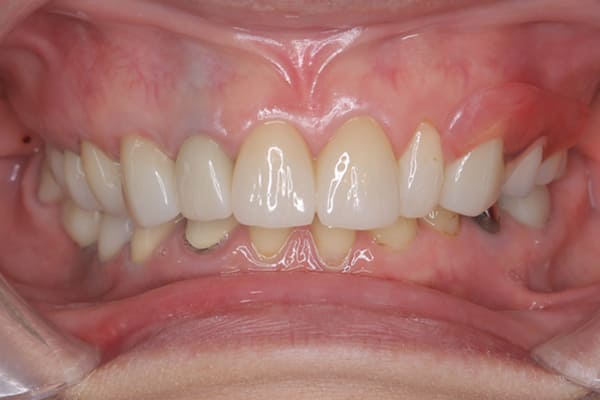

治療前後の口元の比較

こちらは、口を少し開いた時の治療前と治療後の

口元です。

正面から見た時にクラスプが目立たないように、

歯ぐきになじむ素材にて入れ歯を製作し、痛くなく自然に馴染み快適に生活を送れるようになりました。